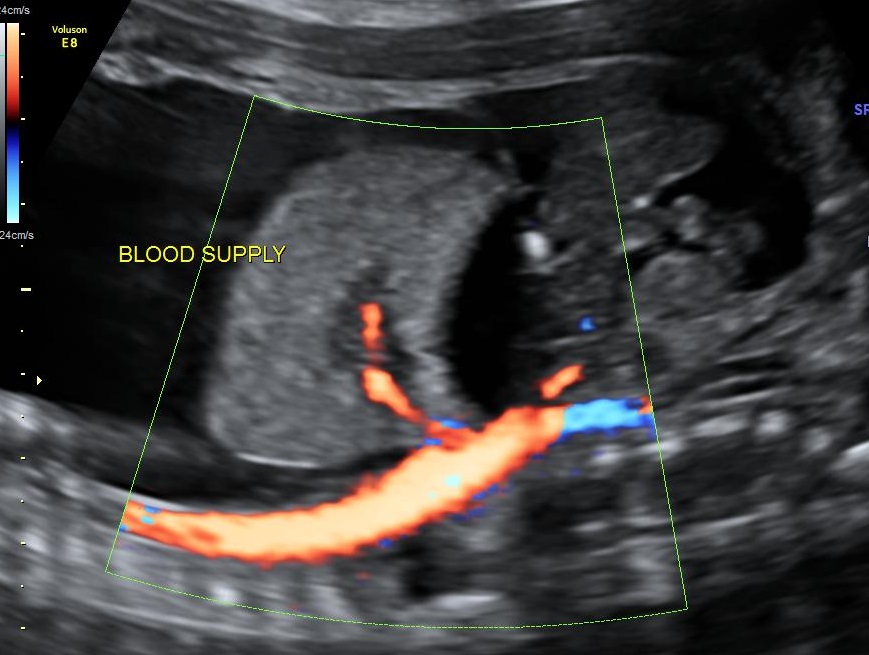

Postnatal CT of the chest reported a 6x3.6x3.3cm ELS in the left lower hemithorax with arterial supply from descending thoracic aorta and venous drainage into the hemiazygos vein (Fig.2). Postnatal management involved skillful ventilation and cardiac stabilization. After reasonable stabilization, the baby underwent sequestrectomy by a conventional left thoracotomy on Day 8 of life (Fig.3). Histologically the mass was confirmed to be BPS.

CT thorax showing the feeding vessel to the ELS from the aorta.